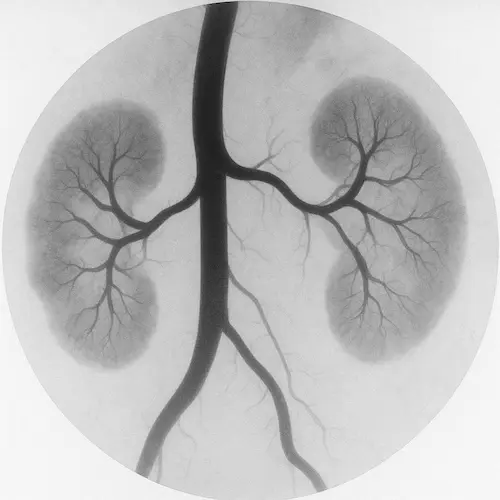

Proteinuria means there is an abnormal amount of protein in the urine. Normally, your kidneys act as a filter to keep important substances like protein in your blood, while removing waste through urine. When the filtering units (called glomeruli) become damaged or inflamed, protein can leak into the urine.

There are small amounts of protein in everyone’s urine occasionally—especially after heavy exercise or illness. But persistent or high levels may indicate a problem with kidney function. Proteinuria is often one of the earliest signs of kidney damage, especially in people with diabetes or high blood pressure.